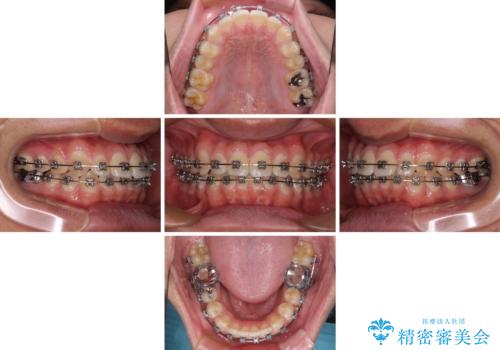

- 矯正装置

- メタルブラケット

- 治療期間

- 1年